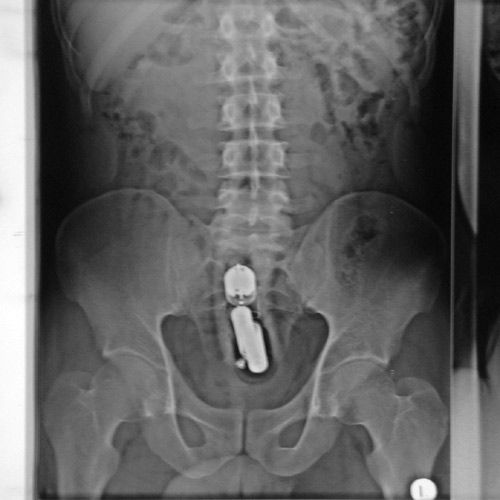

Под рентгеном